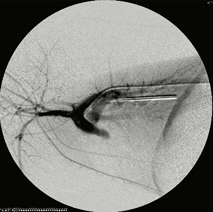

‣バルーンカテーテルによる血栓除去術について

当院では麻酔リスクが生じる点はあるものの、外科的侵襲が少なく短期間で目的を達成できる手技であるため、本術を大動脈血栓塞栓症の第一選択としています。

‣当院での症例紹介